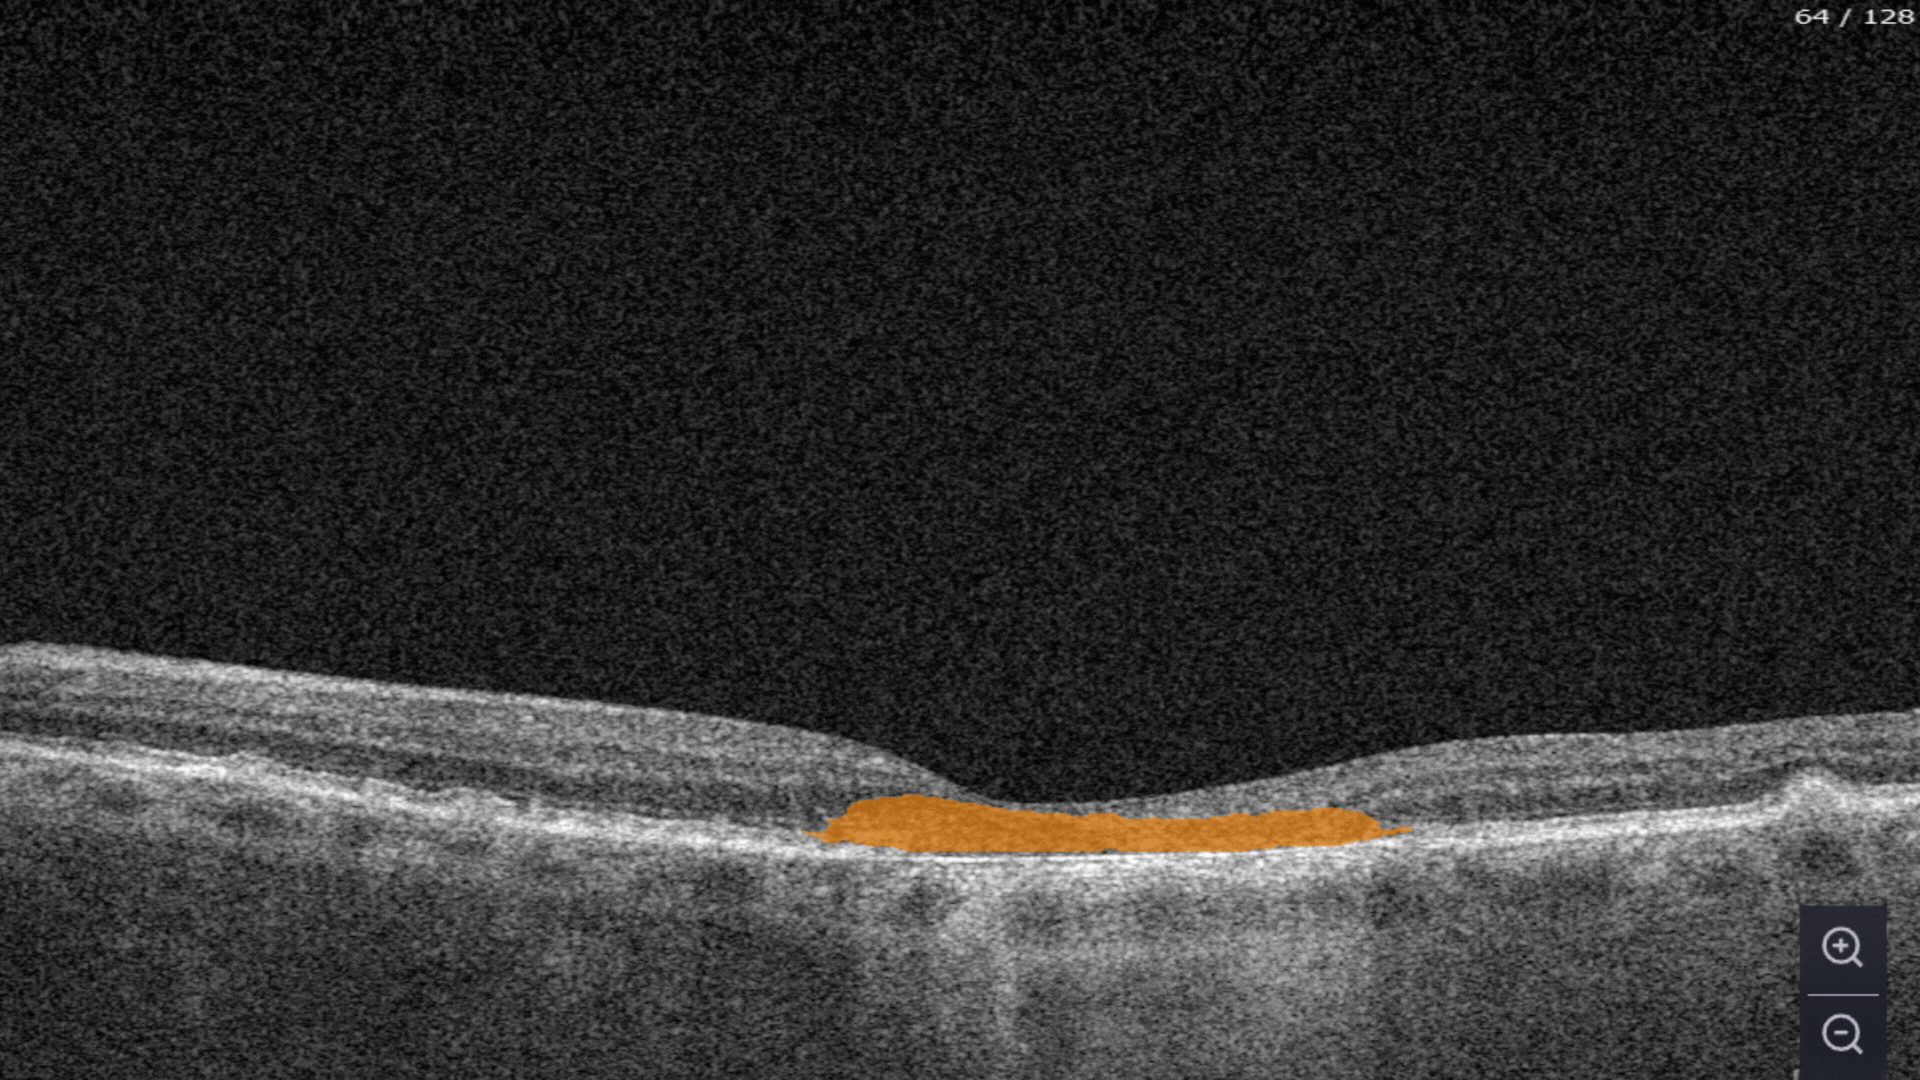

Hypertransmission is one of the first noticeable biomarkers of DR we clearly see with the help of Altris AI.

In the Measurements module, you can assess a dedicated feature for calculating the GA area. This tool automatically calculates the GA lesion by measuring the overlap between two (Hypertransmission and RPE Atrophy) or three biomarkers (adding Neurosensory Retina Atrophy).

The platform allows you to analyze Geographic Atrophy (GA) using each of its biomarkers individually. You can also use a dedicated feature to calculate the total GA area and track its progression over time.